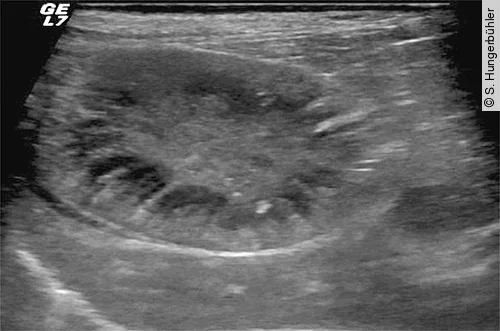

Bei der Sonografie liegt die GB rechts der Medianen und ist in der Regel mittels subkostaler Anschallung gut erreichbar. Im sonografischen Normalbefund stellt sich die GB in der Längsachse als birnenförmige und im Querschnitt als runde anechogene dünnwandige Struktur dar (Abb. 1). Bei tiefbrüstigen Patienten, kleiner Leber und hochdorsaler Lage der GB bedarf es vereinzelt der transinterkostalen Anlotung. Aufgrund der geringen Auflagefläche und des Frequenzspektrums im Bereich um 8–12 MHz sind daher Mikrokonvexsonden besonders für die Untersuchung geeignet.